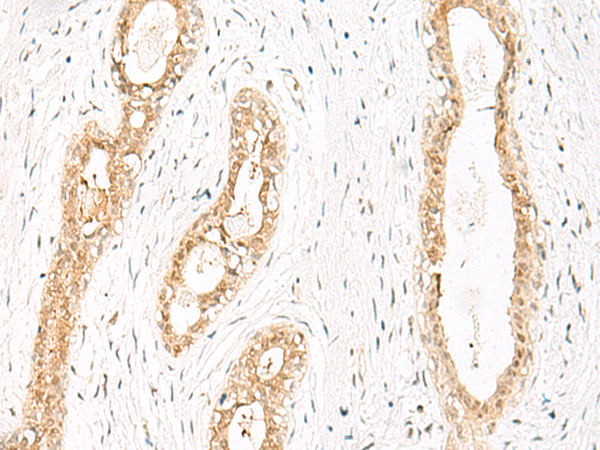

IHC positive control: |

Human thyroid cancer and Human cervical cancer |

IHC Recommend dilution: |

30-150 |